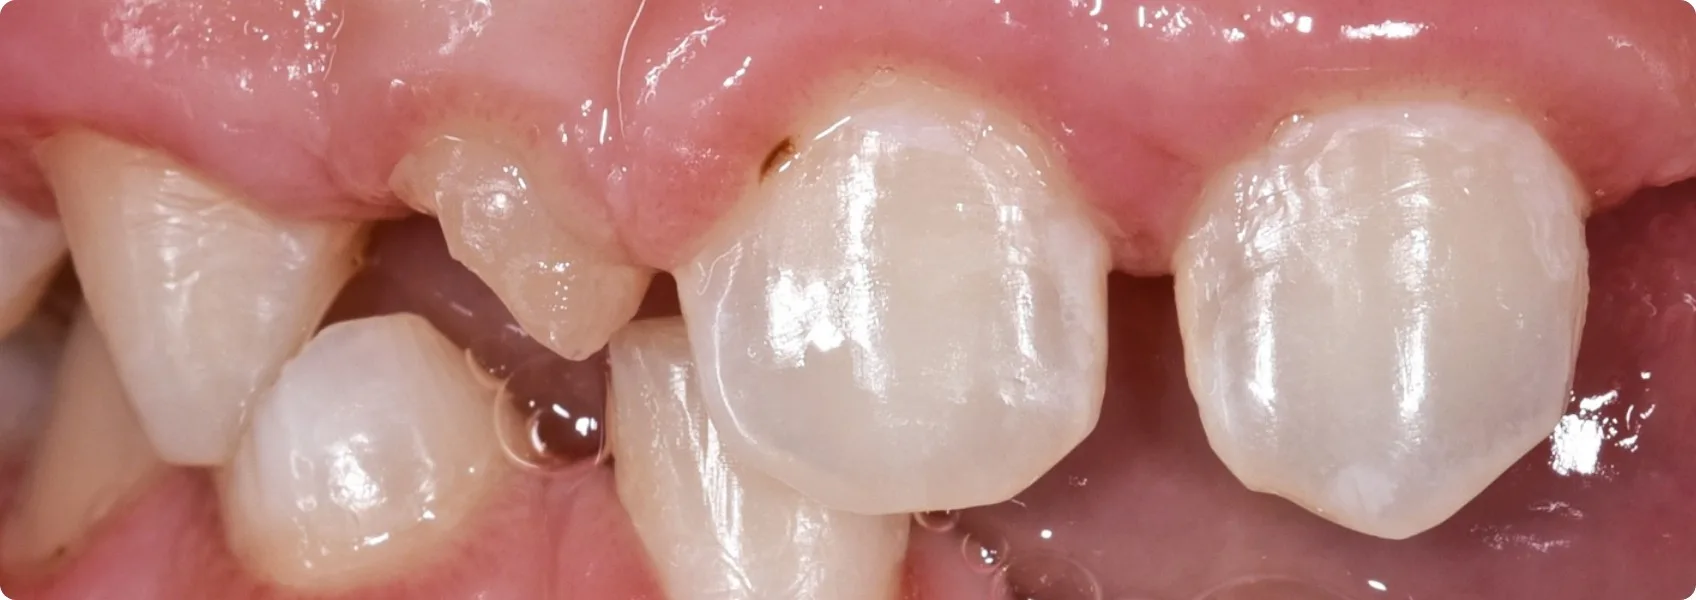

Następnie wysłaliśmy Pacjenta na konsultację chirurgiczną. Nasz chirurg szczękowo-twarzowy, dr n. med. Piotr Chomik, usunął przetrwałe zęby mleczne, które nie wypadły we właściwym czasie. Dziąsła Pacjenta nie miały jednak prawidłowej objętości i konturu.

Aby to naprawić, doktor Piotr wykonał przeszczepy nabłonkowo-łącznotkankowe. Chirurg pobrał niewielkie fragmenty tkanki z podniebienia Pacjenta i precyzyjnie przeszczepił je w miejsca, gdzie dziąsła było za mało. Dzięki tym zaawansowanym zabiegom chirurgicznym uzyskaliśmy piękną, zdrową i estetycznie ukształtowaną linię dziąseł — idealne tło dla przyszłych zębów.

Kiedy Pacjent wrócił do gabinetu protetycznego, doktor Ewa oszlifowała te zęby stałe, które miały posłużyć jako filary pod przyszłą pracę protetyczną. Oszlifowanie (preparacja) jest konieczne, aby zamocować protezę na zębach własnych.